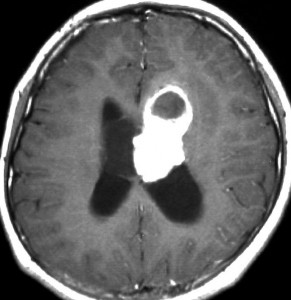

症候性の大きなSEGA

水頭症で発症した10歳の男の子のSEGAです。左側脳室の前角という部位から発生しました。腫瘍は右の脳室にものう胞を形成して,両側のモンロー孔を塞いだために閉塞性水頭症になって,頭痛と嘔吐が出ました。腫瘍の前方には腫瘍内出血もあります。

経皮質法 transcortical approachで摘出した後のMRI画像です。手術中には腫瘍からの出血は多く,深い位置にあり脳質壁を損傷しないように全摘出するのは難しいものでした。その後10年以上たっていますが再発していません。

この例は結節性硬化症を伴わないものでした。